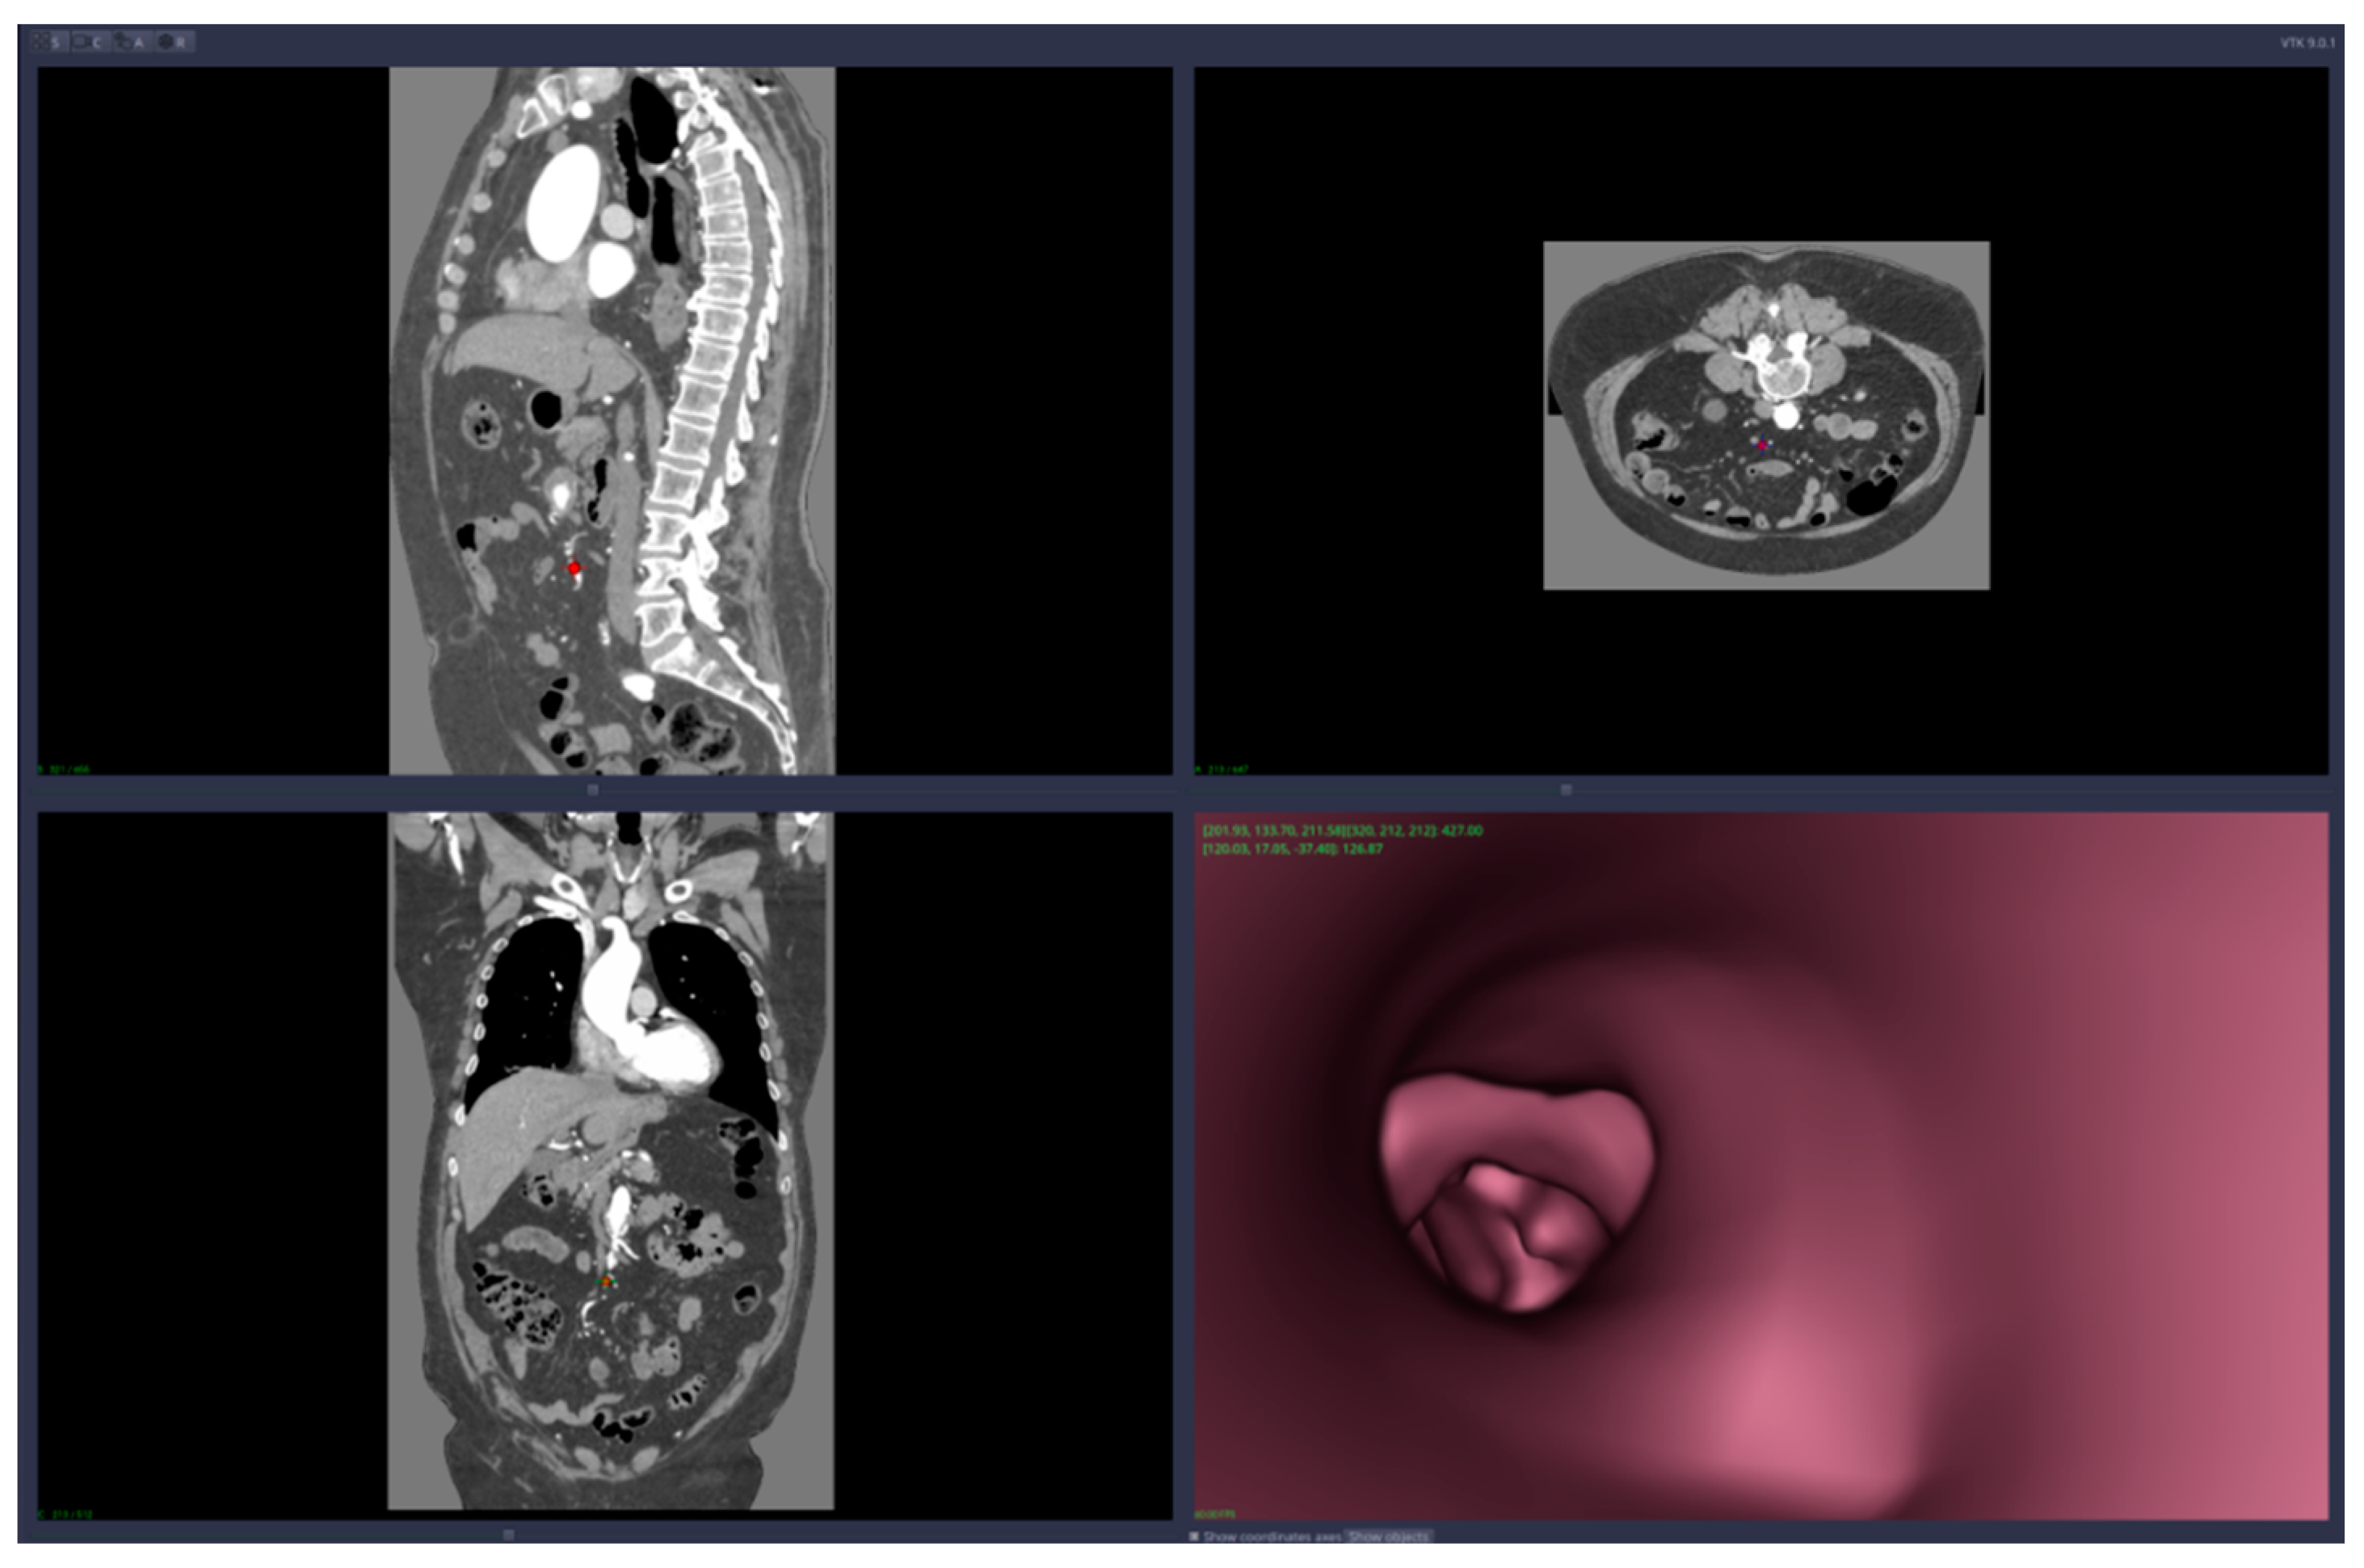

• Virtual angiography—virtual 3D navigation through the mesenteric artery and aneurysm zone (see Figure 3, Figure 4, Figure 5, Figure 6 and Figure 7)

Figure 3. Virtual angiography—“normal” zone of the mesenteric artery, before the aneurysm (direction is opposite to the blood flow).